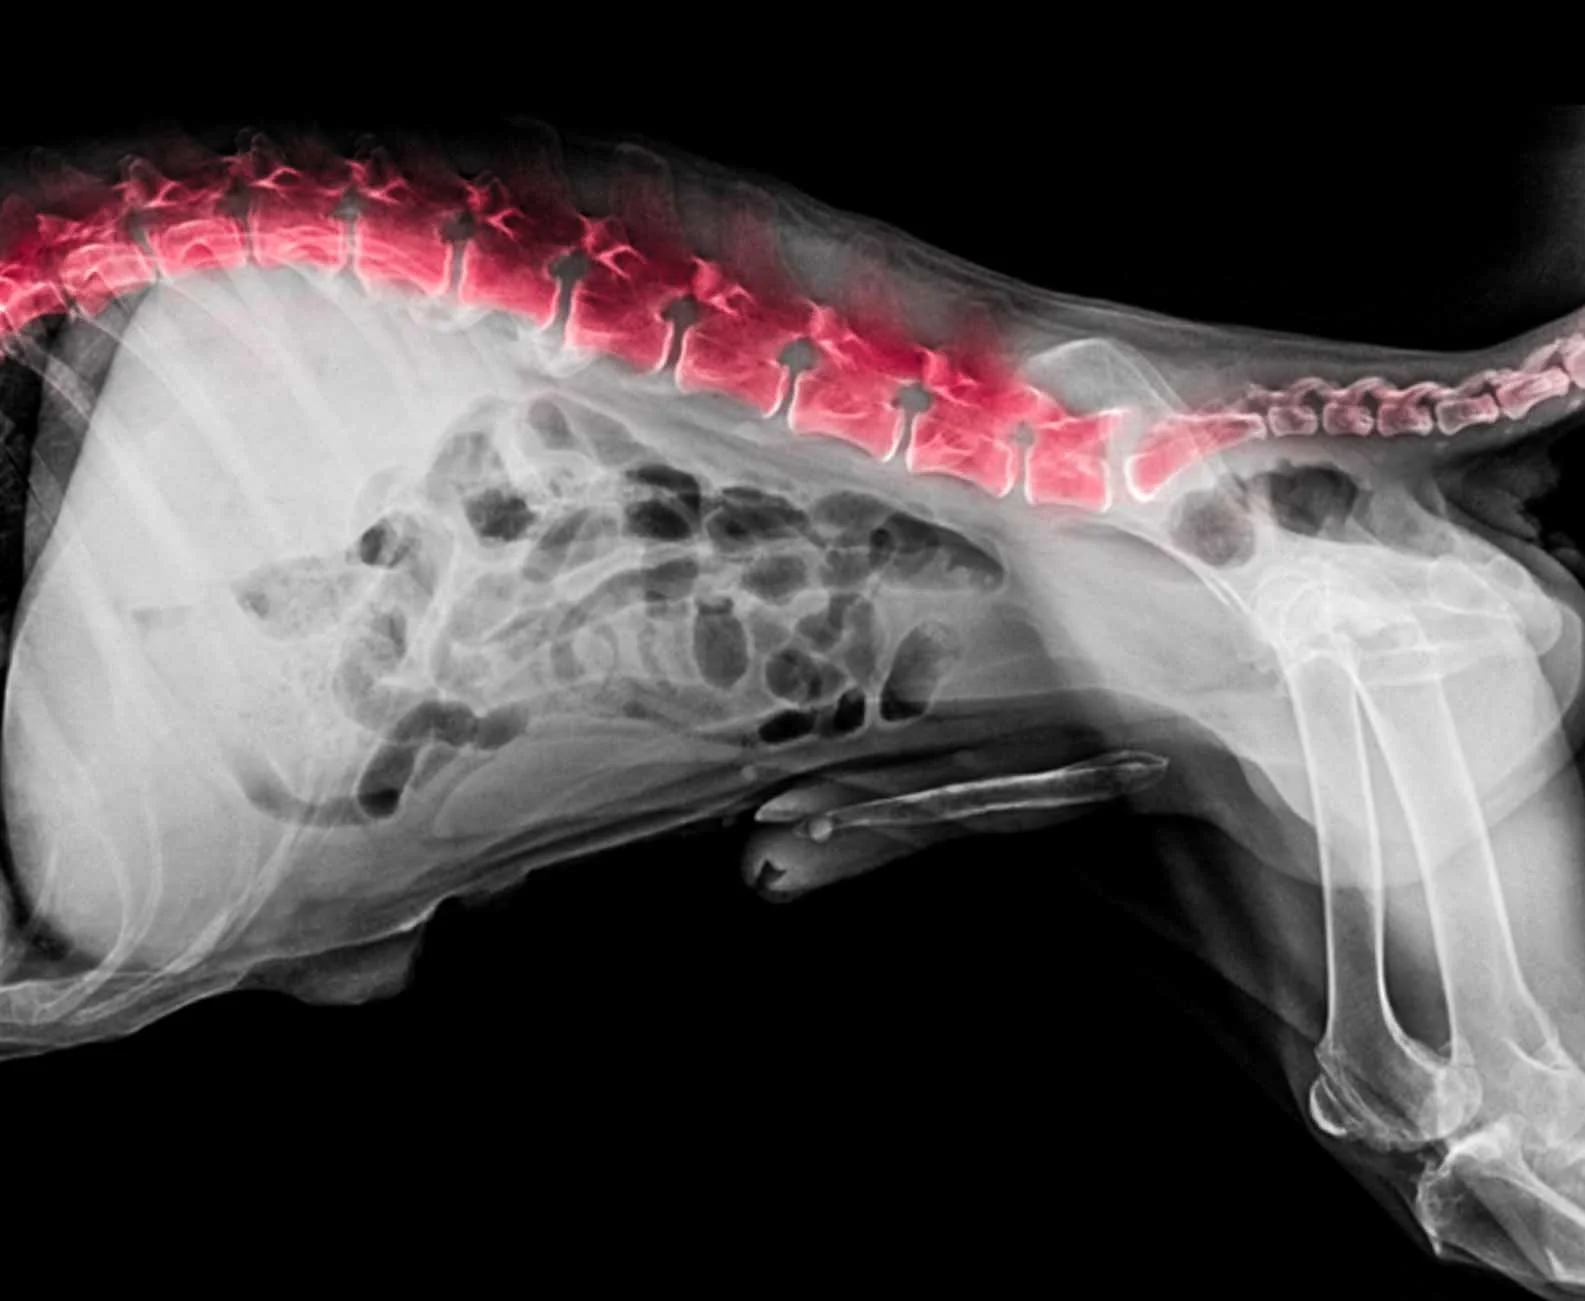

Orthopaedic health relates to the bones, joints, and musculoskeletal structure that support movement and long-term soundness. In a large, powerful breed such as the Cane Corso, correct growth, structure, and management are essential to maintaining mobility, comfort, and working ability throughout life. The conditions outlined below highlight common orthopaedic considerations within the breed and the importance of early awareness, responsible breeding, and appropriate care.

Orthopaedic health underpins the Cane Corso’s ability to move freely, work effectively, and live comfortably throughout life. Sound structure, controlled growth, responsible breeding, and informed ownership all play a vital role in protecting long-term mobility and welfare. By understanding orthopaedic conditions and addressing them early, we can support stronger, healthier dogs and safeguard the future of the breed.